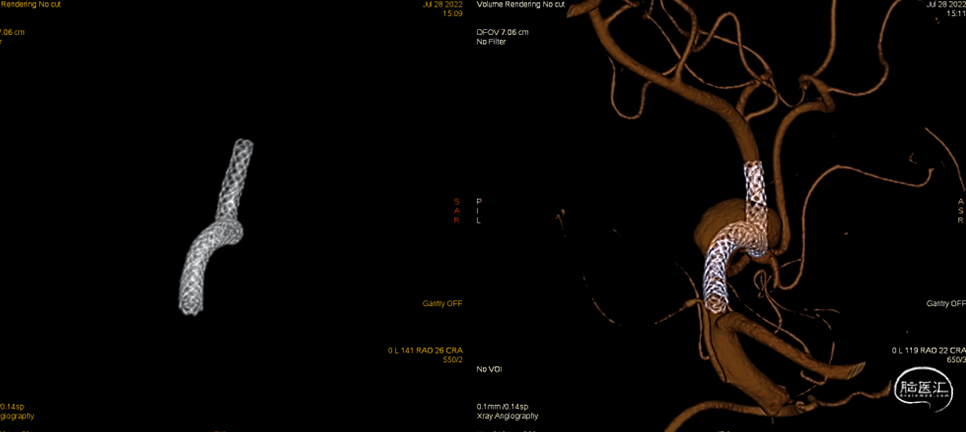

术中造影、减影像及3D-DSA可见支架打开充分。微导丝辅助将Phenom™ 27 微导管送至M3段尽可能远的位置,支撑导管送至M1段尽可能接近动脉瘤。

术中Dyna-CT可见支架打开充分且贴壁良好。

支架远端释放10mm,确认支架打开后整体回撤至计划铆钉点 利用推拉技术让支架在载瘤动脉内充分打开

最后支架尾端减张释放,减影像及Dyna-CT可见支架完全打开且贴壁良好

术中2-D造影可见远端血管通畅良好,晚期动脉瘤内造影剂滞留明显。(07-28)